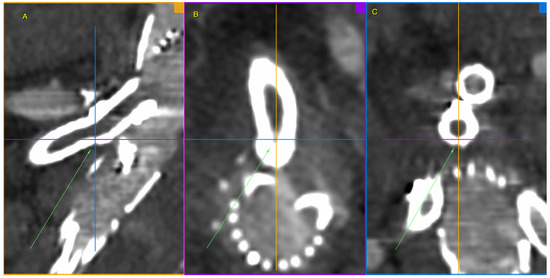

Figure 9. Repaired superior mesenteric artery branch of stent graft in three planes. The mended site is centrally located at the intersection of the lines defining the planes and additionally marked with green arrows. Panel (A)—sagittal projection, panel (B)—axial projection, panel (C)—coronal projection. Control Angio-CT 3D MPR, arterial phase.

Figure 10. Post-intervention final effect. Newly implanted BeGraft Plus in a previously fractured BeGraft in the SMA. The visible image of the “stent within a stent” is marked with an arrow. Control CT—3D reconstruction.